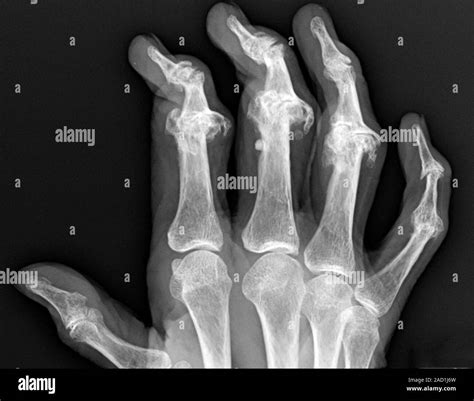

Visual representation of swollen hand joints

• Swelling and Tenderness: Joints may appear enlarged, red, or feel tender to the touch.

• Deformity: In advanced stages, the fingers may become crooked or bony bumps (nodes) may form near the joints.